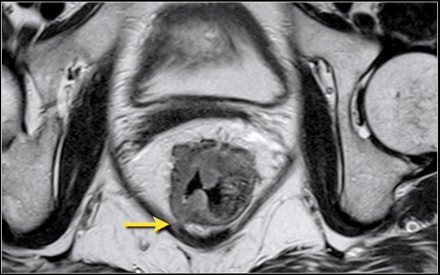

Hình 5. Khối ung thư trực tràng giai đoạn T3 MRF-

- T4: được chia T4a: khối u trực tiếp xâm lấn thanh mạc hoặc cân mạc treo trực tràng. T4b: khối u xâm lấn trực tiếp hoặc dính vào các tạng, cơ quan khác.